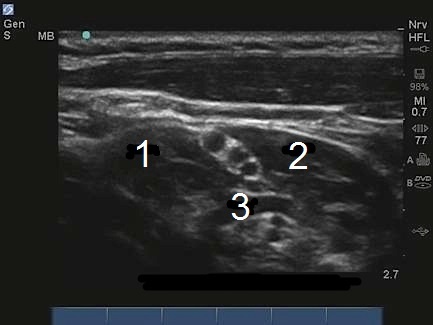

M-Turbo: Brachial Plexus Interscalene Level 5

1. MSM

2. ASM

3. Artery